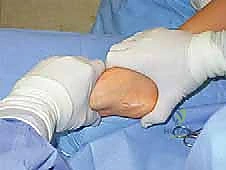

القدم الحنفاء الجوفاء الروحاء هي تشوه معقد في القدم يؤثر على وظيفتها وحركة المريض. يتضمن علاجها تصحيحًا جراحيًا دقيقًا يعتمد على خبرة جراح العظام. الأستاذ الدكتور محمد هطيف في صنعاء يقدم حلولًا متقدمة لتشخيص وعلاج هذه الحالة، مستعيدًا وظيفة القدم الطبيعية وراحة المريض.

الخلاصة الطبية السريعة: القدم الحنفاء الجوفاء الروحاء (Pes Equinocavovarus) هي تشوه معقد وثلاثي الأبعاد في القدم والكاحل، يؤثر بشدة على وظيفة القدم، توازن المريض، وقدرته على المشي الطبيعي. يتضمن علاج هذه الحالة تصحيحًا جراحيًا دقيقًا ومتدرجًا يعتمد بشكل كلي على خبرة ومهارة جراح العظام المتخصص. يُعد الأستاذ الدكتور محمد هطيف في صنعاء المرجع الطبي الأول والوجهة الموثوقة لتقديم حلول متقدمة لتشخيص وعلاج هذه الحالة المعقدة، مستخدمًا أحدث التقنيات الجراحية العالمية لاستعادة وظيفة القدم الطبيعية، تخفيف الألم، وإعادة الأمل وراحة المريض للعودة إلى حياته الطبيعية.